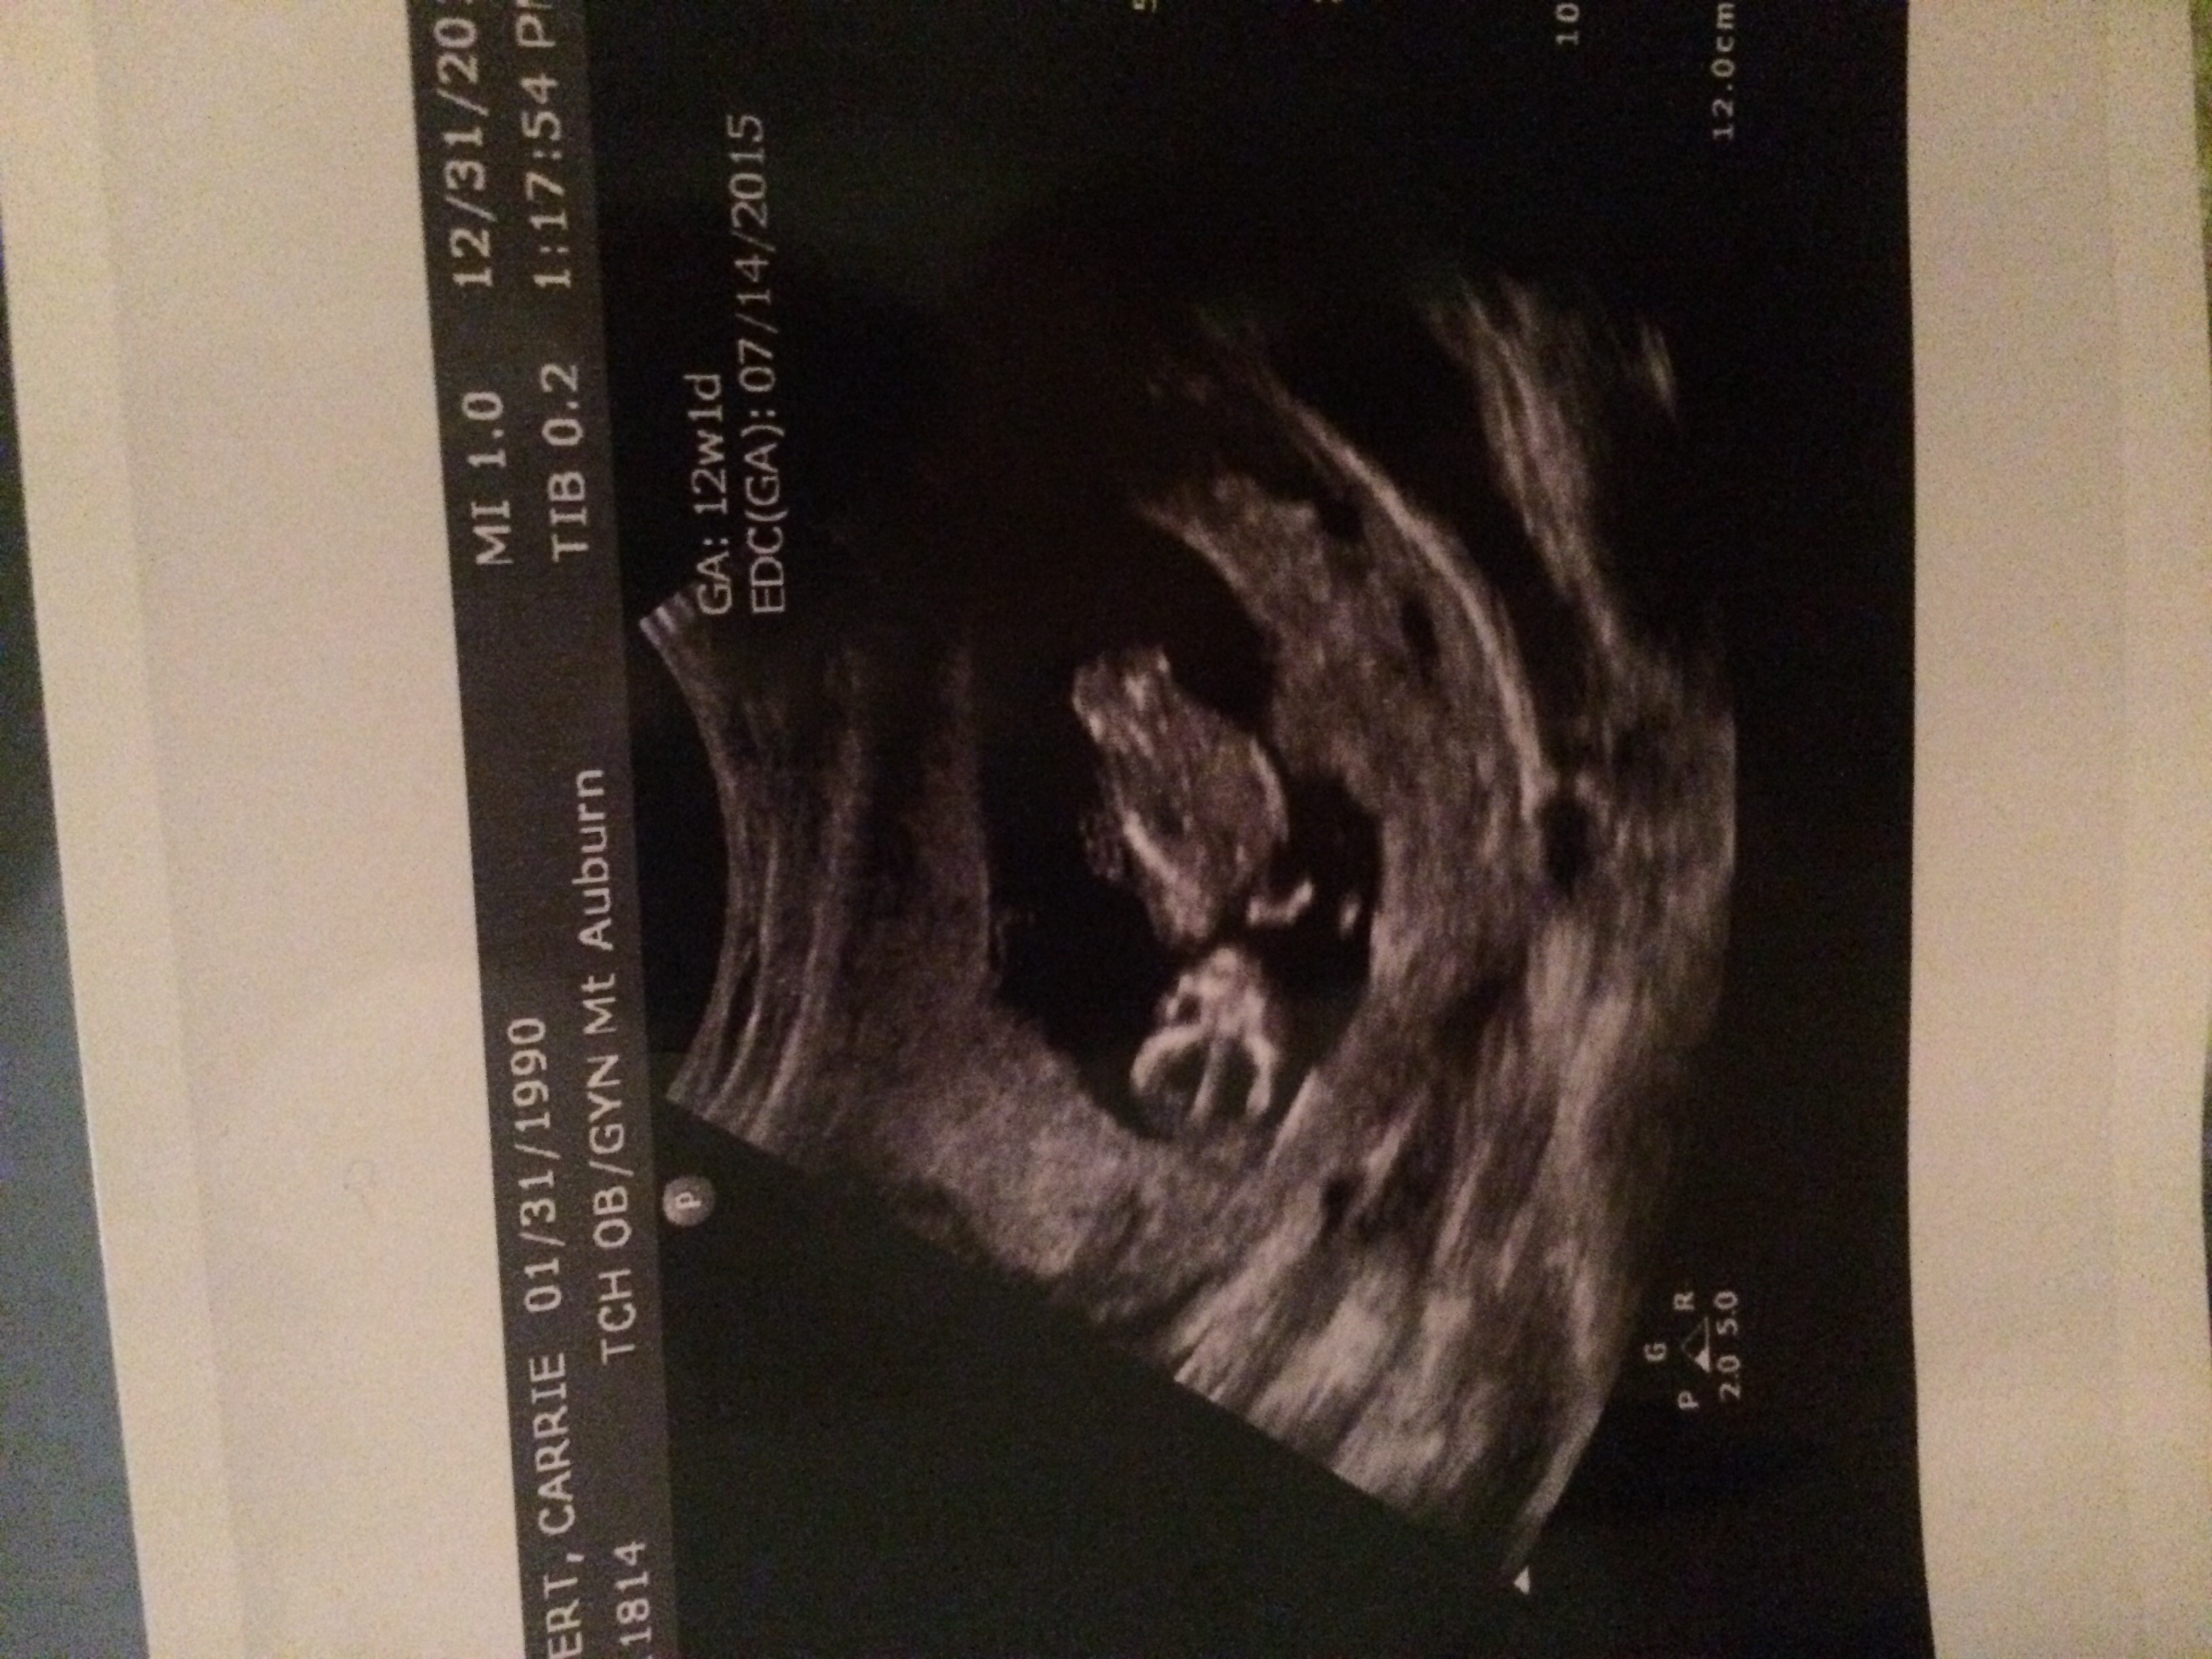

Can you tell if it's a boy or girl from these pictures??